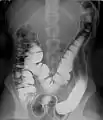

Clisma cu bariu cu dublu contrast - Utilizarea contrastului pozitiv și negativ